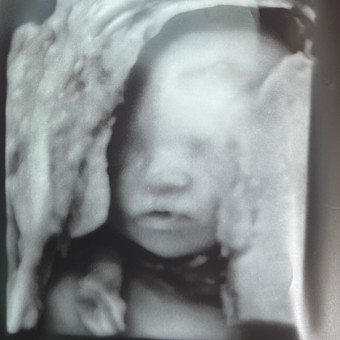

Maliek’s Registry🩵

Abigale Elliott & David Jean Pierre

Bradenton, FL

June 27, 2026